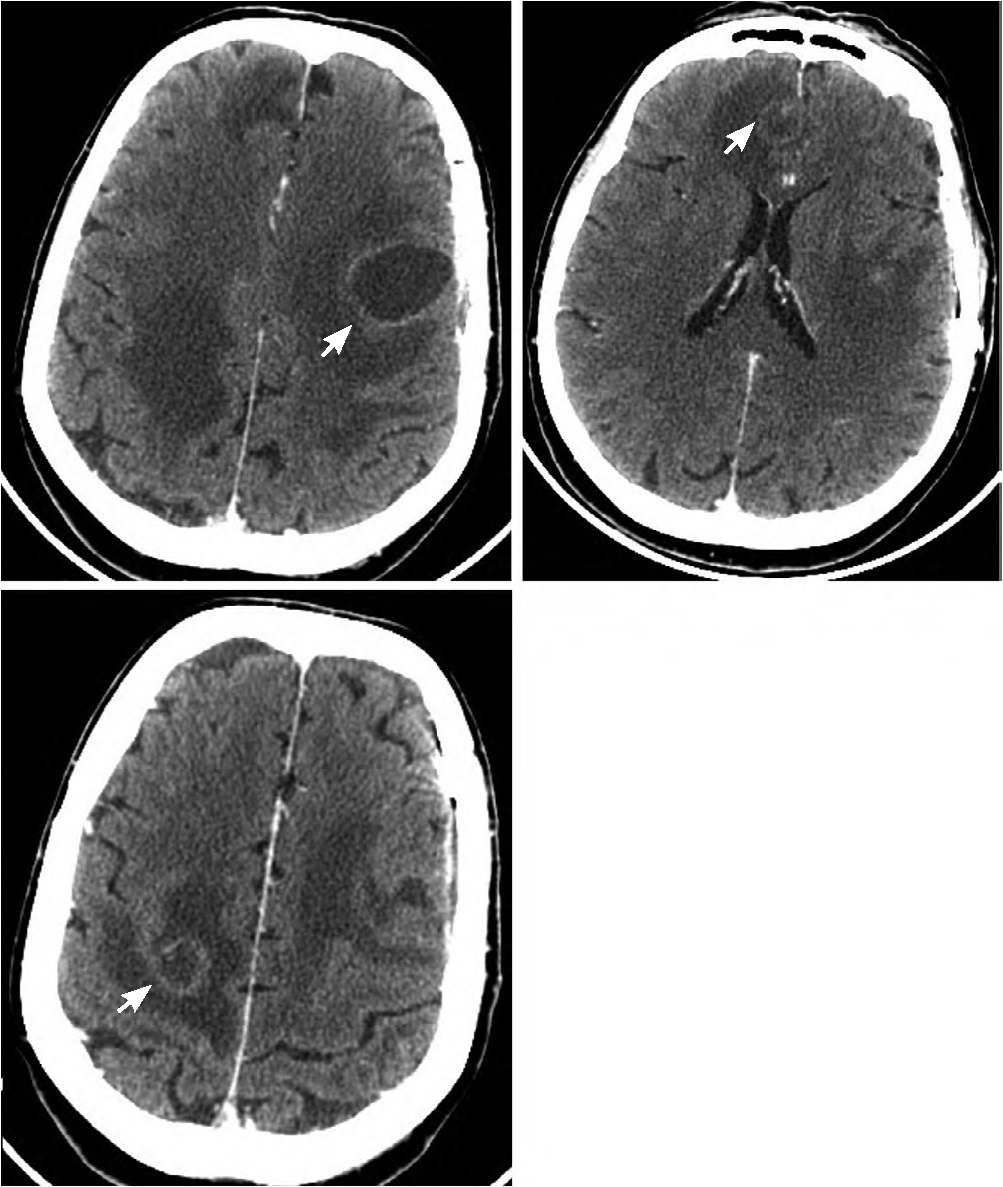

Пациентка Я., 39 лет, доставлена в приёмный покой бригадой скорой помощи с серией судорожных приступов. При поступлении предъявляла жалобы на головную боль и слабость в левых конечностях. Считает себя больной около 1 мес, когда появилась и стала нарастать головная боль, отмечались подъёмы температуры тела до 37,5–37,8ºС, затем за неделю до обращения наросла слабость в левой руке. В день госпитализации у пациентки развился генерализованный судорожный приступ. В анамнезе полинаркомания на протяжении 15 лет, ВИЧ-инфекцию отрицает. На момент осмотра: сознание ясное, критика снижена, отмечается левосторонний гемипарез со снижением мышечной силы до 2 баллов в руке и 4 баллов в ноге. В приёмном покое выполнена МСКТ головного мозга, по результатам которой выявлено кистозно-солидное объёмное образование глубинных отделов правой лобной доли с выраженным перифокальным отёком, кольцевидно накапливающее контрастное вещество. Максимальный размер очага 4,8 см (рис. 1).

Рис. 1. МСКТ головного мозга пациентки Я. с контрастным усилением.

Определяется объёмное образование глубинных отделов правой лобной доли, кольцевидно накапливающее контрастное вещество с выраженным перифокальным отёком и дислокацией срединных структур.

Fig. 1. Contrast-enhanced brain MSCT image of patient Ya.

A mass deeply in the right frontal area, with a ring contrast enhancement, a significant perifocal edema, and dislocated midline structures.